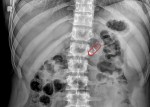

A new auto-injecting pill might soon become a replacement for subcutaneous injection treatments. The idea for this so-called robotic pill came out of a research project around eight years ago from InCube Labs — a life sciences lab operated by Rani Therapeutics Chairman and CEO Mir Imran, who has degrees in electrical and biomedical engineering … Continue reading How Rani Therapeutics’ robotic pill could change subcutaneous injection treatment